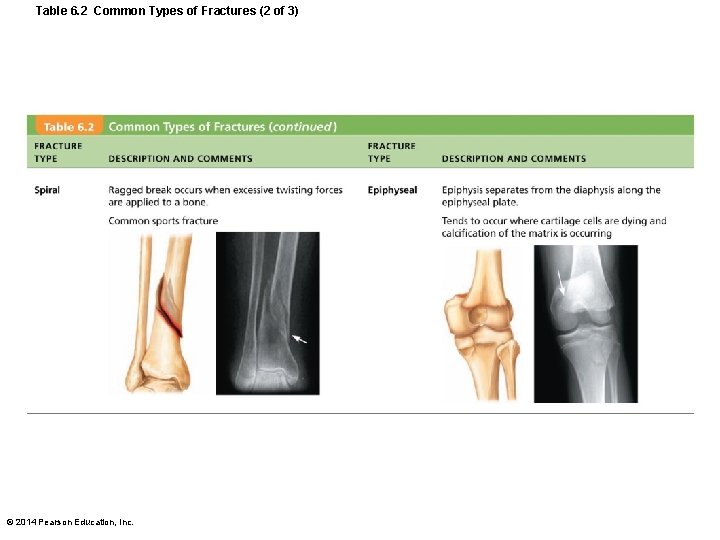

Table 6. 2 Common Types of Fractures (2 of 3) © 2014 Pearson Education, Inc.